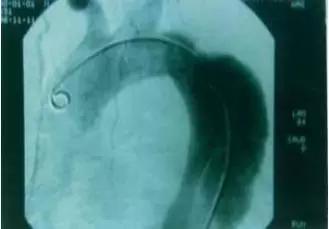

在M型超声中可见主动脉根部扩大,夹层分离处主动脉壁由正常的单条回声带变成两条分离的回声带。

在二维超声中可见主动内分离的内膜片呈内膜摆动征,主动脉夹层分离形成主动脉真假双腔征。有时可见心包或胸腔积液。

多普勒超声不仅能检出主动脉夹层分离管壁双重回声之间的异常血流,而且对主动脉夹层的分型、破口定位及主动脉瓣返流的定量分析都具有重要的诊断价值。